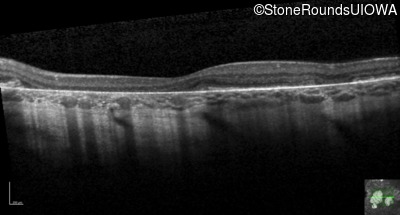

Age at visit: 33 years

Age at visit: 33 years (Visit 2)

This 31 year old woman had subtle macular abnormalities discovered incidentally earlier that year. Her medical history at the time was unremarkable except for gestational diabetes during her most recent pregnancy. Five years later she was diagnosed with type 2 diabetes managed with oral medication. Two years later she developed sufficient hearing loss that hearing aids were required. Her acuity remained 20/20 OU at that time.